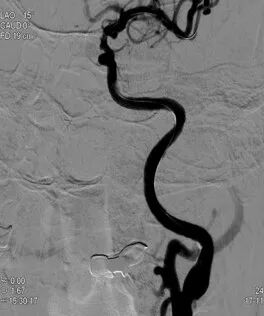

◆ 球囊扩张释放支架。

导丝怎么扩重磅!NOVA颅内药物球扩支架湖北首例植入!_https://www.jmylbn.com_新闻资讯_第11张

透视下扩张球囊并释放支架

◆ 左侧颈内动脉C4段狭窄解除。

导丝怎么扩重磅!NOVA颅内药物球扩支架湖北首例植入!_https://www.jmylbn.com_新闻资讯_第12张

支架释放回收球囊后造影

◆ 远端分支显影良好。

导丝怎么扩重磅!NOVA颅内药物球扩支架湖北首例植入!_https://www.jmylbn.com_新闻资讯_第13张

左侧颈内动脉系统造影